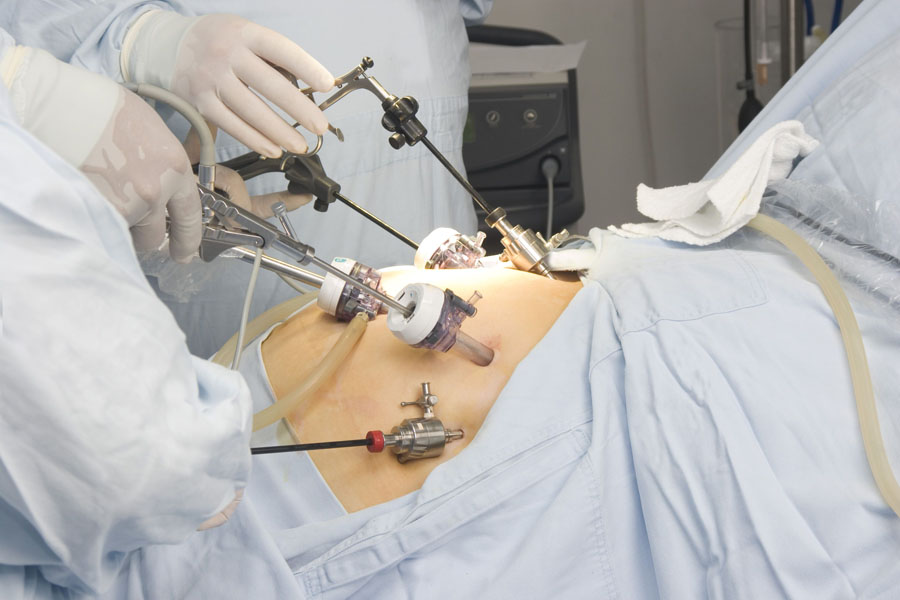

Los avances médicos encaminados a mejorar el tratamiento de los pacientes y su calidad de vida han impulsado el desarrollo de las técnicas laparoscópicas. En muchas operaciones ya ha sido aceptada la cirugía laparoscópica como primera opción.

En la actualidad existen múltiples procedimientos disponibles en cirugía de la obesidad. La banda gástrica ajustable laparoscópica (BGAL) ha sido una de las técnicas bariátricas más utilizadas. Ha demostrado ser un procedimiento seguro con una tasa de mortalidad muy baja y pocas complicaciones perioperatorias mayores.